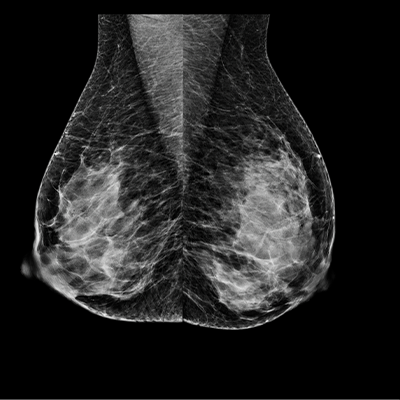

La Mammographie

Une mammographie est une radiographie des seins. Elle a pour but principal la détection du cancer mammaire à un stade précoce (le cancer du sein est le premier cancer chez la femme). Actuellement les mammographies sont entièrement numérisées.

Les images sont réalisées dans un mammographe par une manipulatrice en radiologie, en position debout, torse nu. Pour obtenir des images de qualité et réduire la dose d’irradiation, il est indispensable de réaliser une compression du sein. Chaque sein est comprimé de façon successive dans le sens haut-bas et selon un axe oblique. Ceci n’est pas douloureux. Vous avez la possibilité de discuter avec la manipulatrice en radiologie au cours de l’examen.